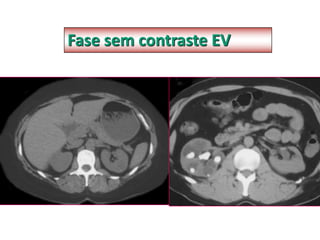

Fase sem contraste EV

FASE SEM CONTRASTE

• Importante para avaliação das demais fases

• Pacientes alérgicos

• Protocolo de urolitíase